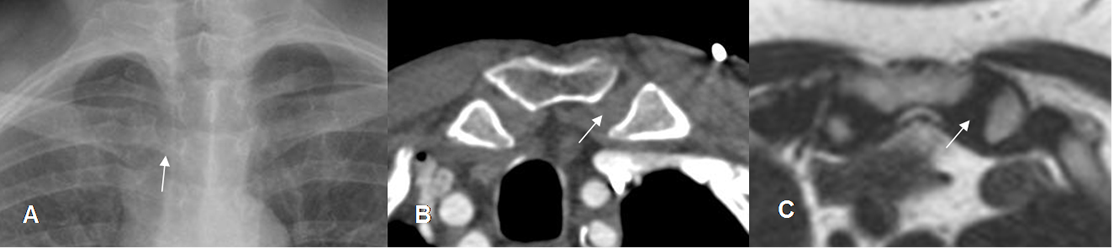

Fig 15. Articulación esternoclavicular normal.

A: Rx AP. Articulación con interposición de varias estructuras óseas.

B: TAC axial en ventana de tejido y C: RM axial en T2. Articulación sinovial, con tejido blando que corresponde al cartílago, entre las estructuras óseas.